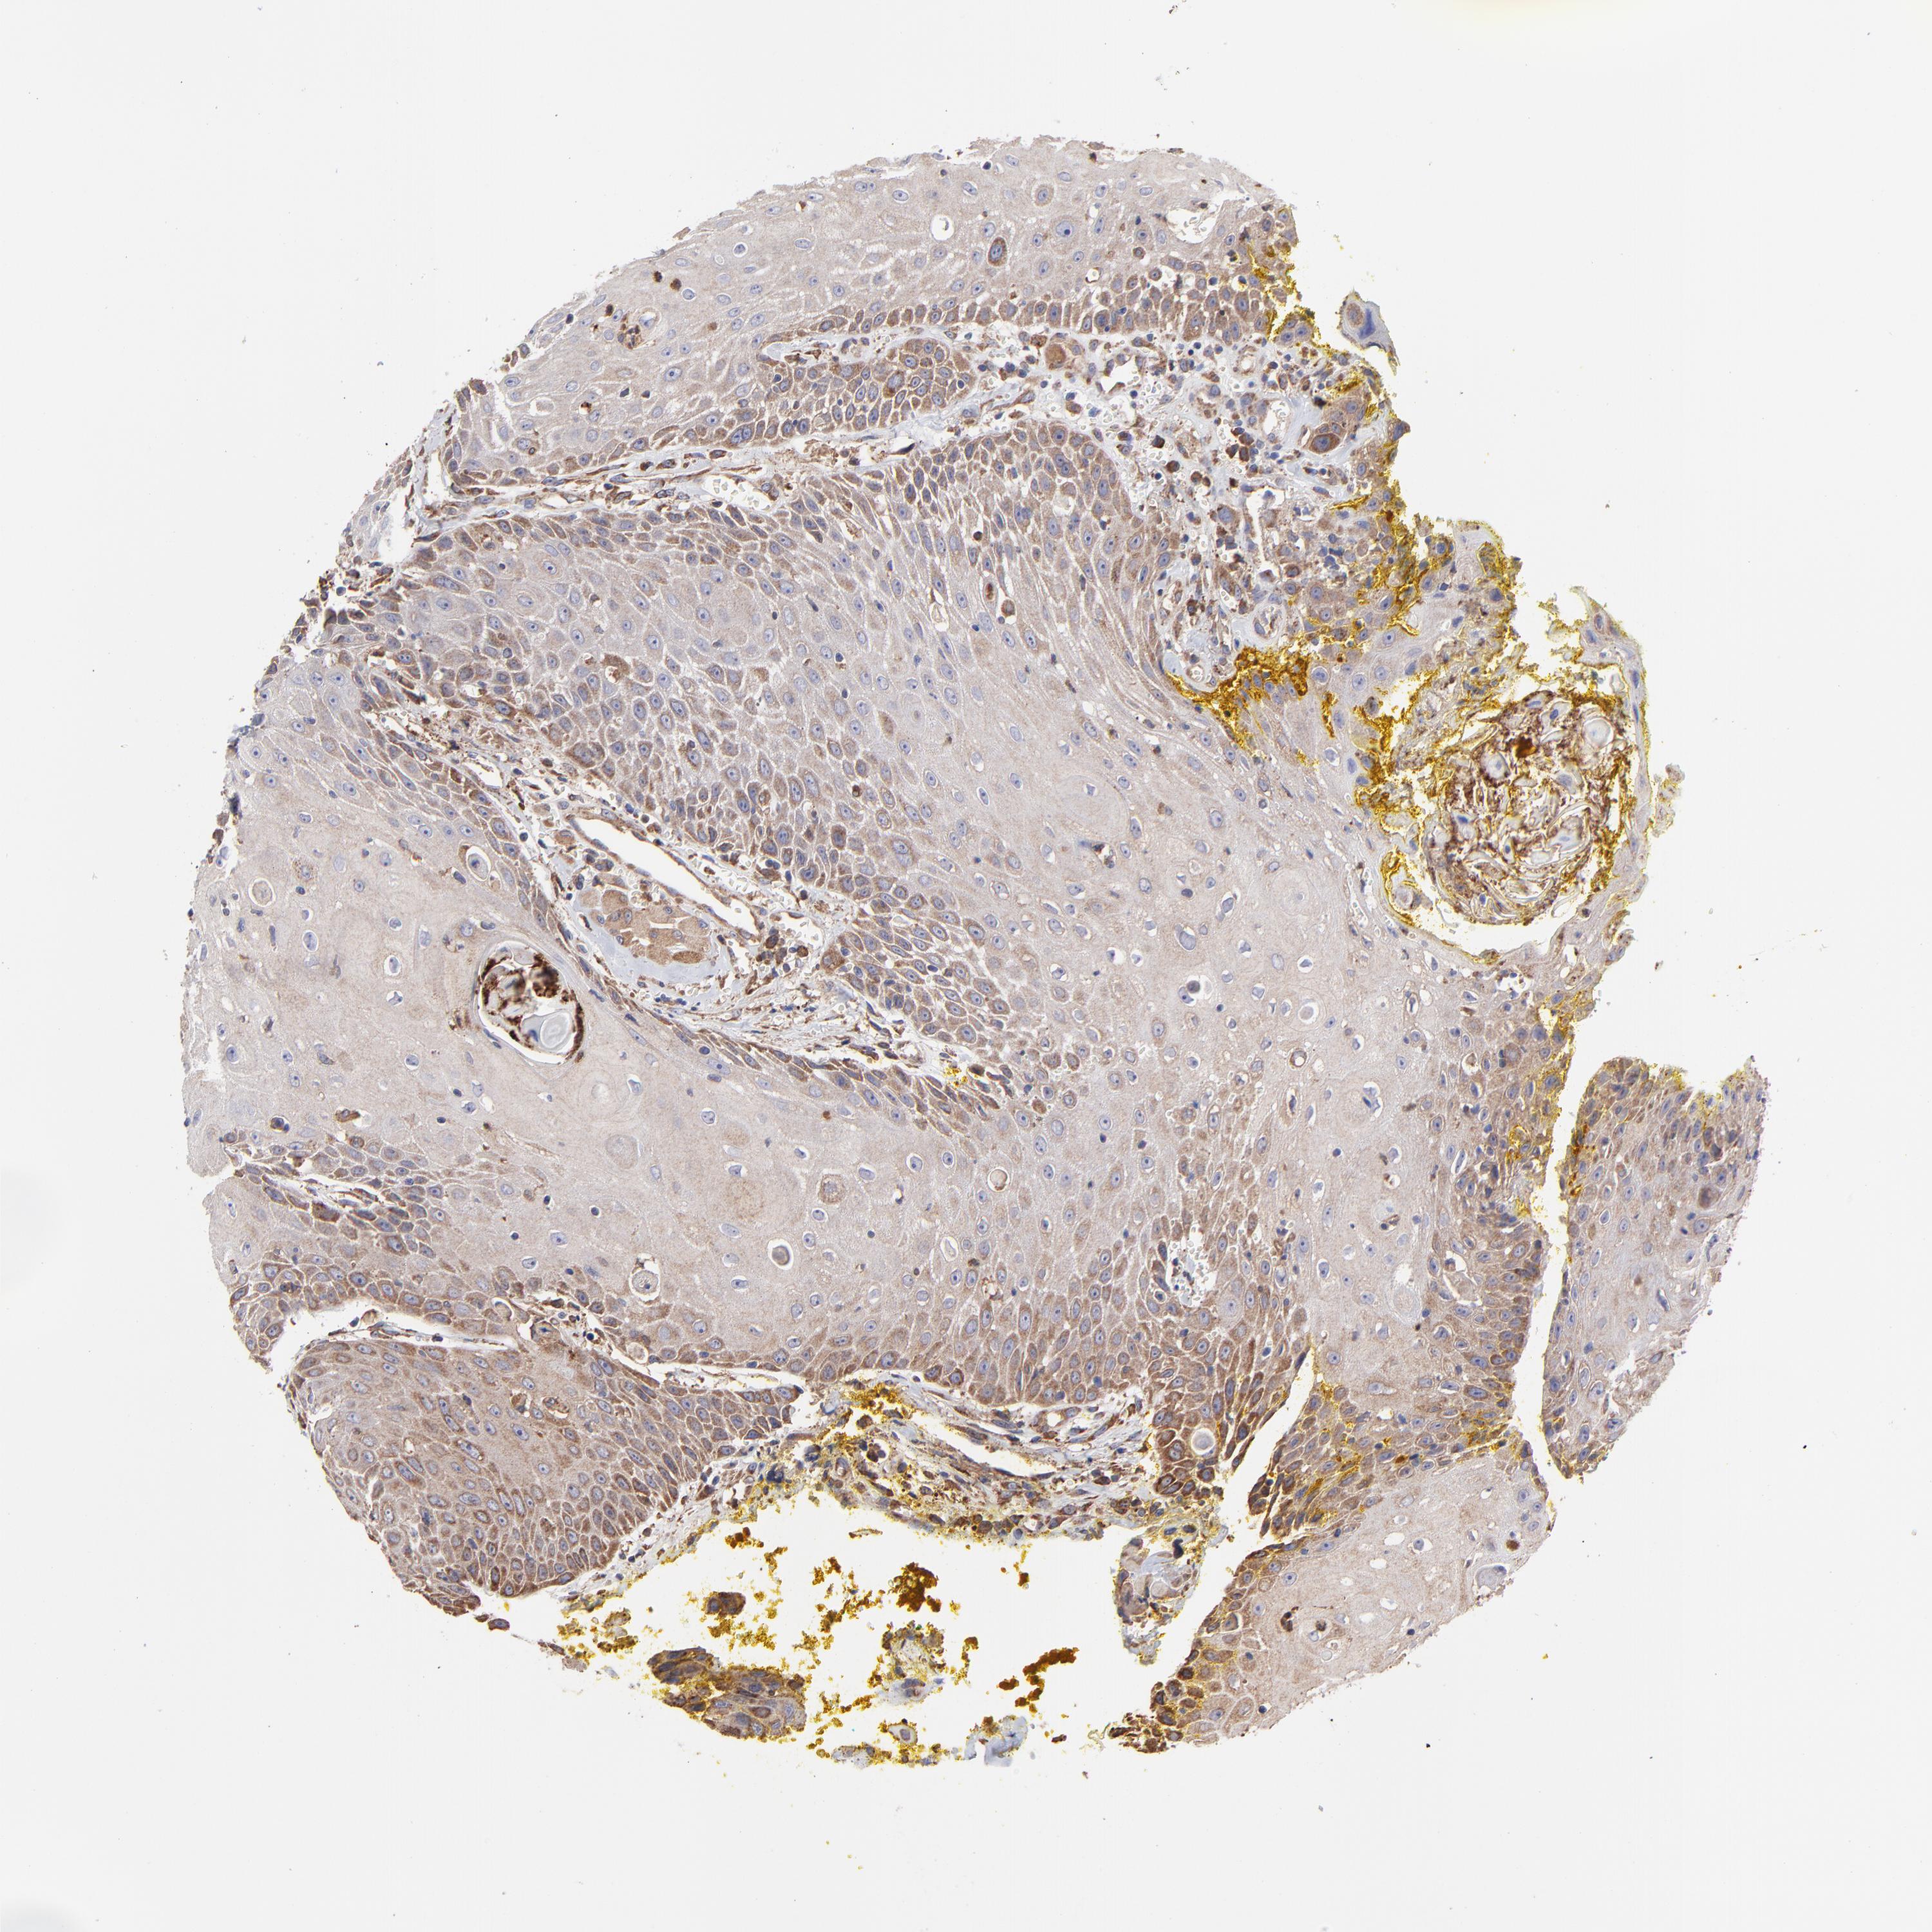

HEAD AND NECK CANCER - Protein expressioni

A mouse-over function shows sample information and annotation data. Click on an image to view it in a full screen mode. Samples can be filtered based on level of antibody staining by selecting one or several of the following categories: high, medium, low and not detected. The assay and annotation is described here.

Note that samples used for immunohistochemistry by the Human Protein Atlas do not correspond to samples in the TCGA dataset.

Antibody stainingi

Antibody staining in the annotated cell types in the current human tissue is reported as not detected, low, medium, or high, based on conventional immunohistochemistry profiling in selected tissues. This score is based on the combination of the staining intensity and fraction of stained cells.

Each image is clickable and will lead to virtual microscopy that enables deeper exploration of all samples and also displays staining intensity scores, fraction scores and subcellular localization as well as patient and tissue information for each sample.

Antibody HPA002117

Staining

High

Medium

Low

Not detected

Intensity

Strong

Moderate

Weak

Negative

Quantity

>75%

75%-25%

<25%

None

Location

Nuclear

Cytoplasmic/membranous

Cytoplasmic/membranous,nuclear

Squamous cell carcinoma, NOS

Squamous cell carcinoma, metastatic, NOS